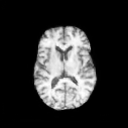

The results presented in Table 1 and 2 show our proposed method’s performance on unconditional 3D brain MR and chest CT image generation. Our proposed approach not only outperforms most comparing methods in FID and MS-SSIM metrics, it also has the lowest inference GPU memory footprint at a resolution of and was the only diffusion-based method that could be trained at a resolution of . Operating in the wavelet domain and profiting from the reduced spatial dimension also results in a relatively short inference time of / at the respective resolutions. Compared to the results presented in [23], we did not find that incorporating wavelet information into the network’s feature space (WavU-Net) increased the model’s performance. Qualitative results of our proposed method (WDM) are shown in Fig. 2 and 3. A qualitative comparison of samples produced by all evaluated methods can be found in the Supplementary Material.